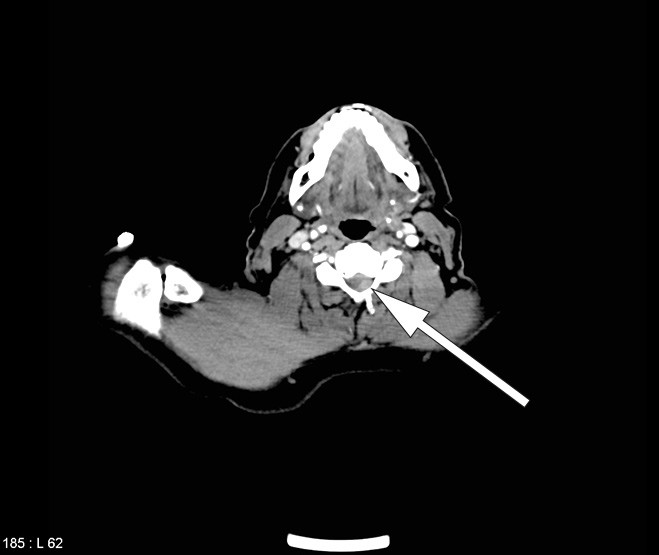

The CT scan of the total aorta on admission, prior to thrombolysis, was initially interpreted as normal, apart from a subtotal stenosis in the subclavian artery. However, a new examination of cervical sections with some change in the grey-tone scale (window/level) revealed that the epidural haemorrhage was already visible before the thrombolysis (Fig. 3).

Figure 3  CT image which with retrospective interpretation was found to show the epidural haematoma at the time of admission